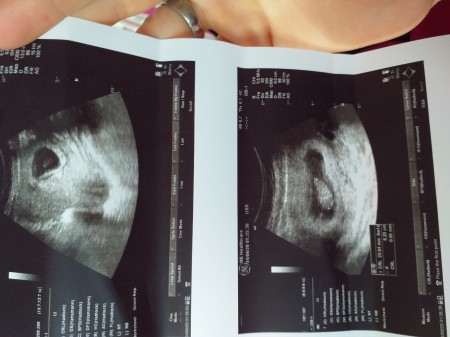

Ikiz Bebek Ultrason

Ikiz Bebek Ultrason.